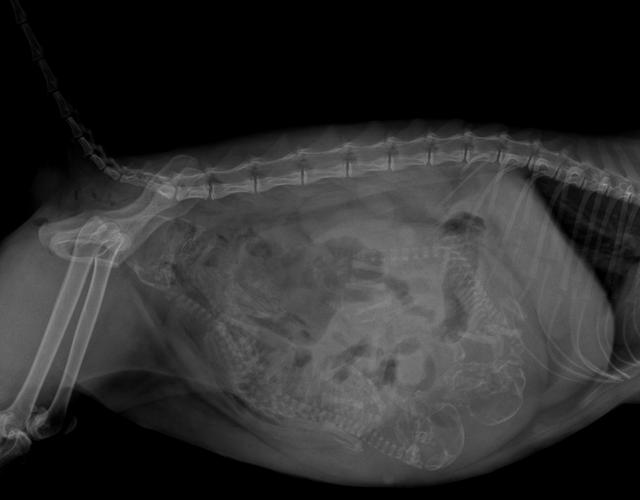

5, 孕期在45天左右,借助X光影像检查,通过胎儿的脊椎线和头部位置,确定胎儿数目,以及胎儿在母体内的摆位,作为评估是否会发生难产的依据,当然,辐射量不会对母体和胎儿造成危害。